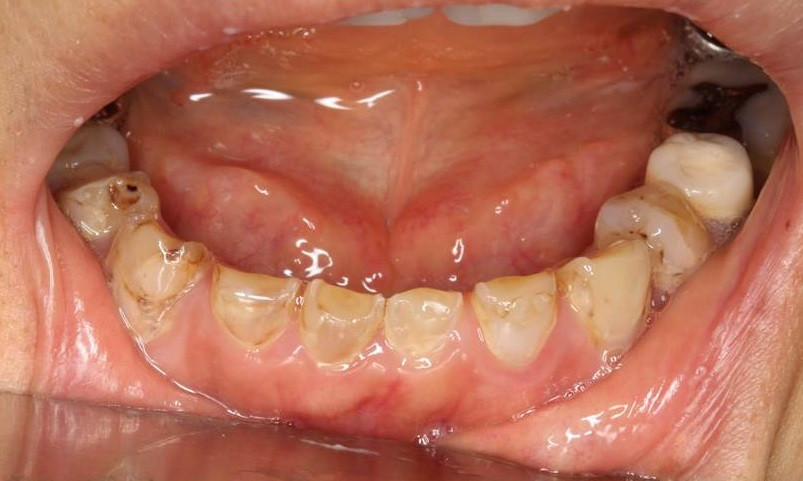

写真画像は,長期に渡り摂食障害があった患者様のお口の様子です。もし,「歯が小さくなってきたかな?」,「歯が削れてきてしみるようになってきたかな?」などの症状でお困りの際には,是非,グランツ歯科クリニックまでご相談ください。

“Tooth Wear”自体は加齢と共に進行する生理的現象ではありますが、高齢者で重篤度が増し,若年者では軽症である傾向にあるため、早期発見・早期治療が鍵となります。“Tooth Wear” を進行させる加速因子としては,胃食道逆流症,薬剤投与による唾液減少,酸性食品の大量摂取,摂食障害に伴う嘔吐などが挙げられ,過度な咬耗症を併発した重症例では全顎的な補綴介入が必要となる場合があります。